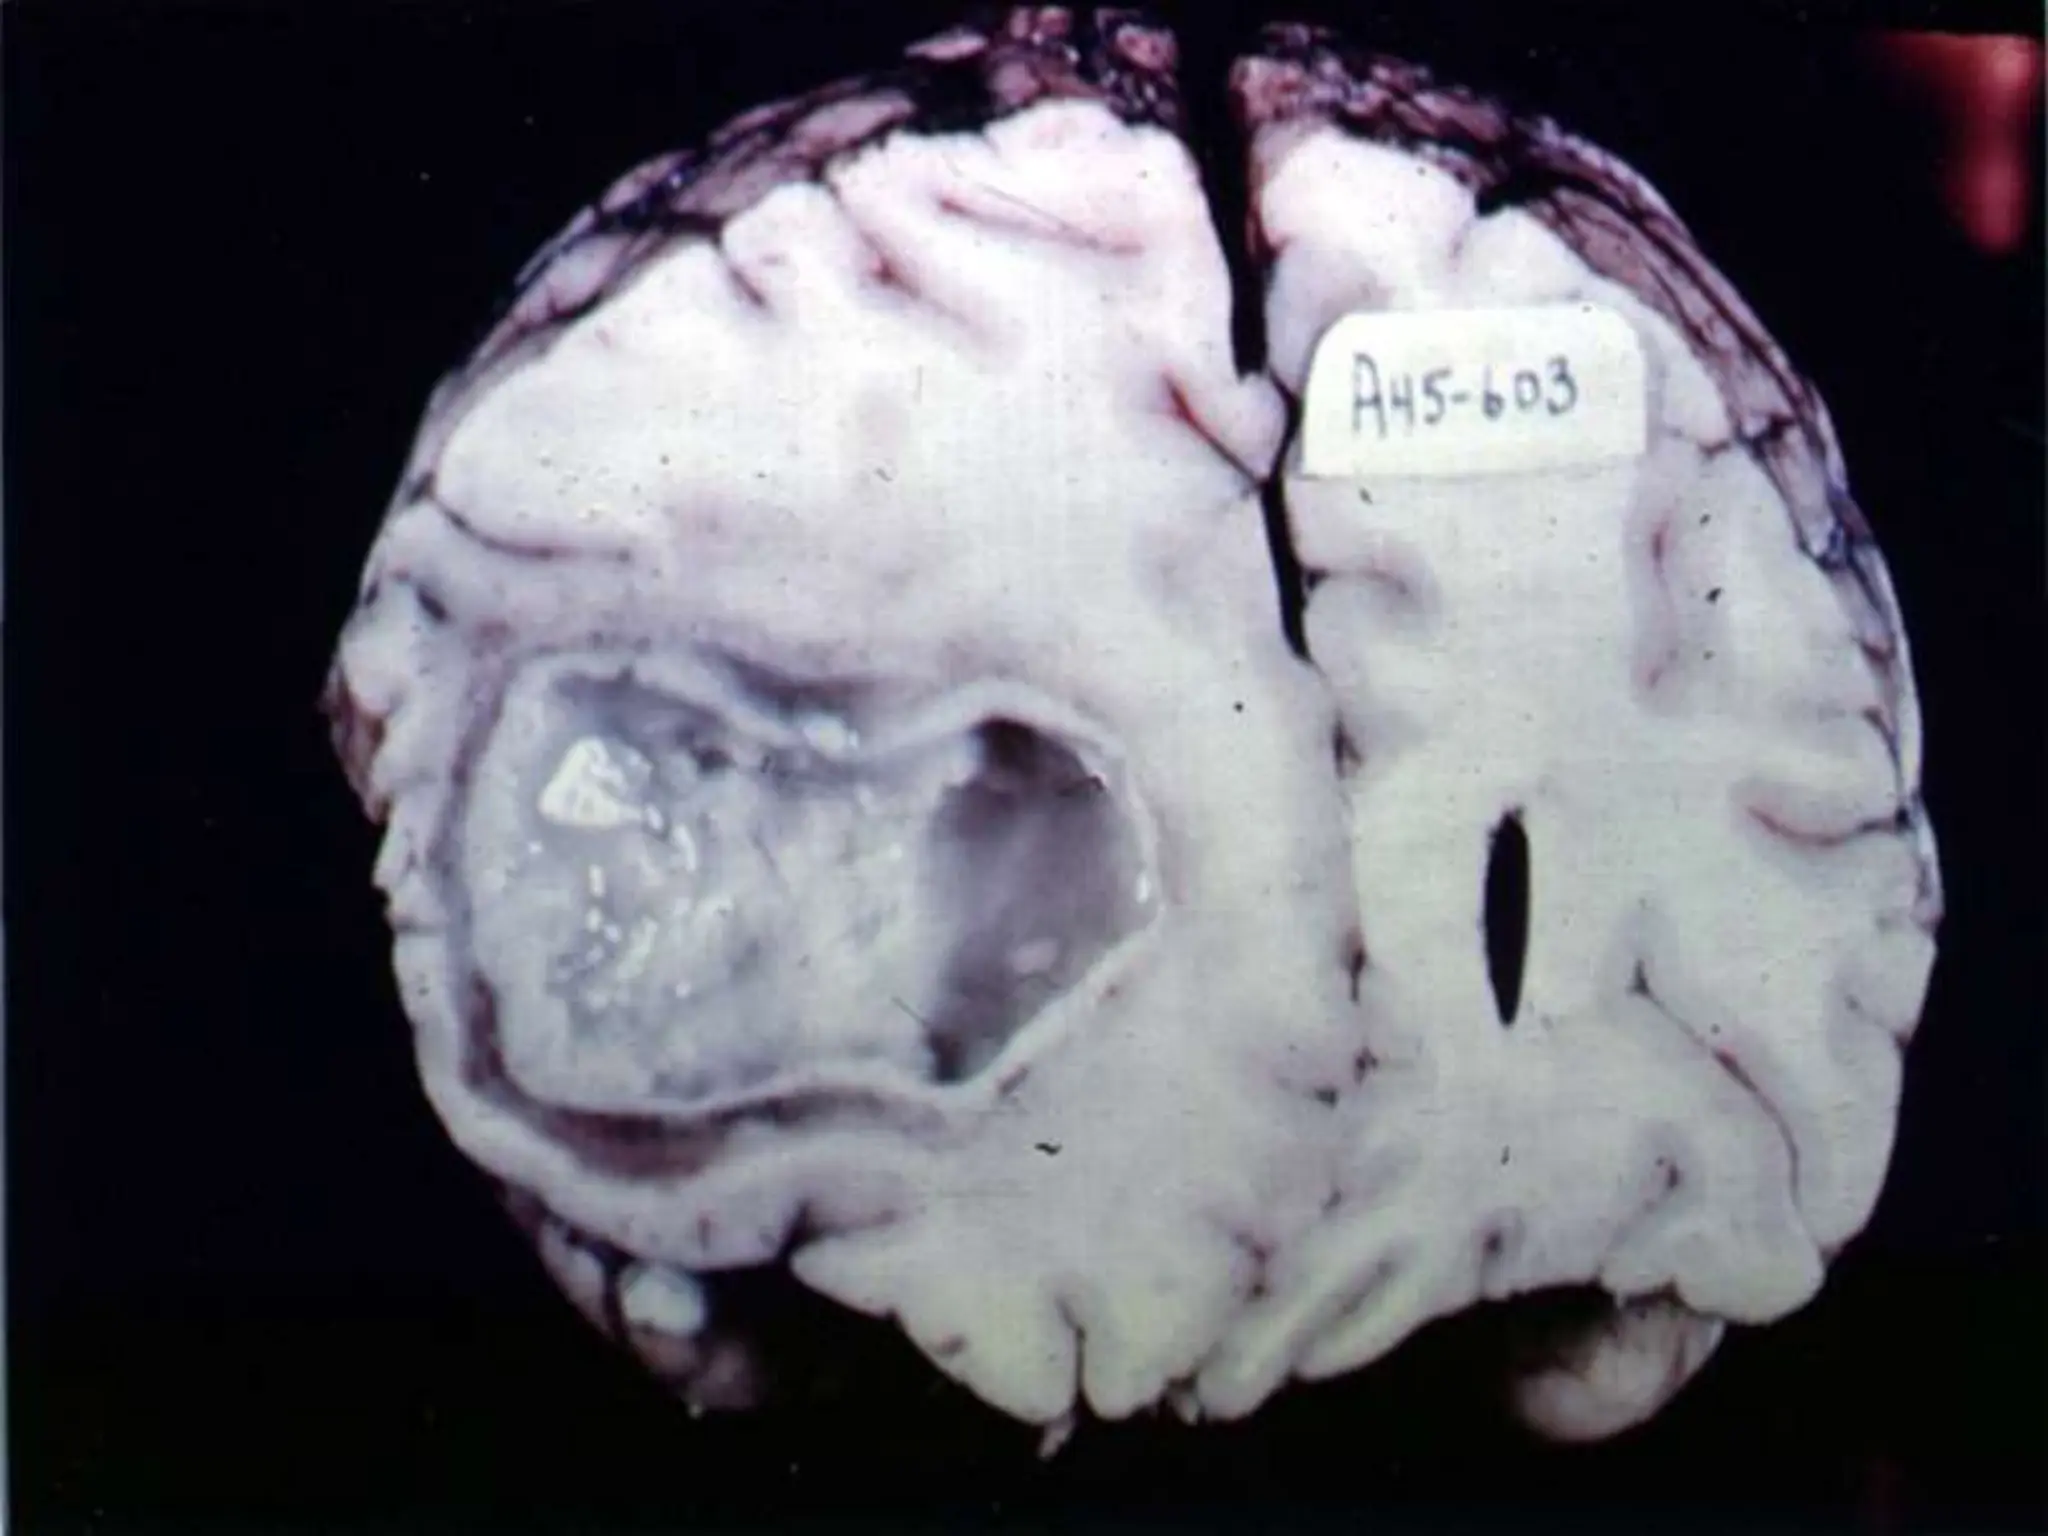

GLIOBLASTOMA

Gross:

 Variegated  firm &

white; soft & yellow

(necrosis); cystic

degeneration,

hemorrhages

 Apparently well

demarcated

 always infiltrates

adjacent brain

Microscopy:

 Anaplastic

astrocytoma + necrosis

& endothelial cell

proliferation.

 Necrosis:

serpentine/

geographic necrosis.

Geographic Necrosis

 Highly malignant

tumor cells crowd

along edge of necrosis

 ‘pseudopalisading’.

GLIOBLASTOMA Gross:  Variegated firm & white; soft & yellow (necrosis); cystic degeneration, hemorrhages  Apparently well demarcated  always infiltrates adjacent brain

Microscopy:  Anaplastic astrocytoma +necrosis & endothelial cell proliferation.  Necrosis: serpentine/ geographic necrosis.

Geographic Necrosis  Highlymalignant tumor cells crowd along edge of necrosis  ‘pseudopalisading’.